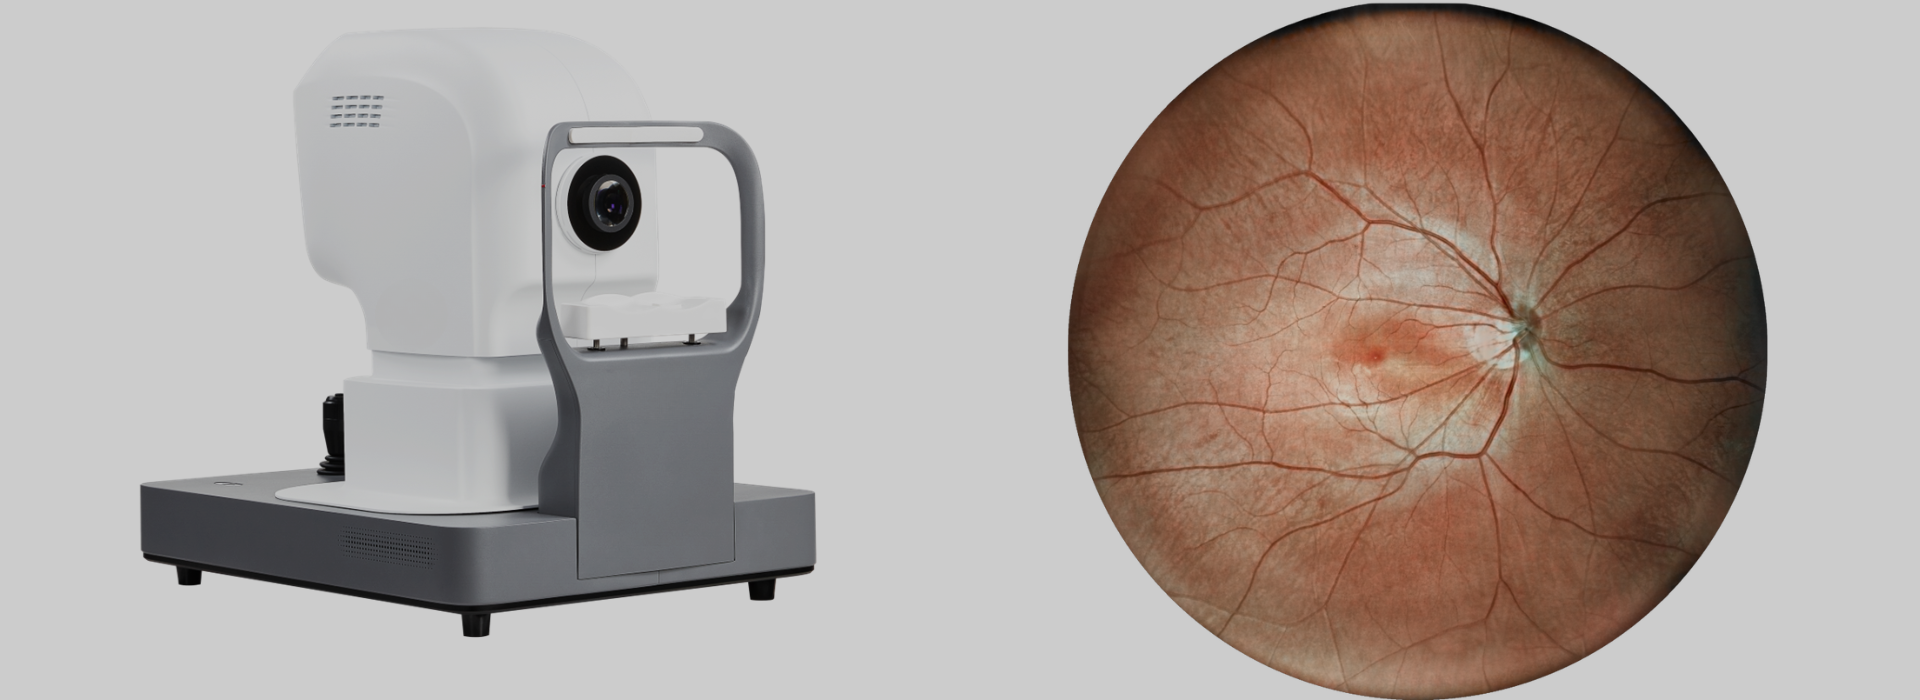

Advantages of Laser Scanning Light Source

The light source of a fundus camera determines its effectiveness. The LED light used in optical fundus cameras is highly irritating, has a narrow range, and lacks penetration. The laser light source used in the laser fundus camera has low stimulation, a wider field of view, and strong penetration, enabling in-depth observation. Laser fundus imaging provides richer information and a more accurate diagnosis.